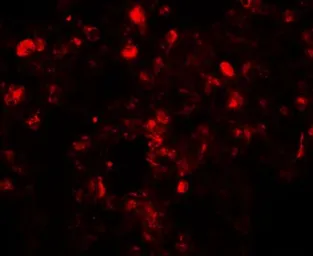

Translin antibody

Cat. No. GTX31440

ApplicationsWB IHC-P ELISA

ReactivityHuman, Mouse, Rat